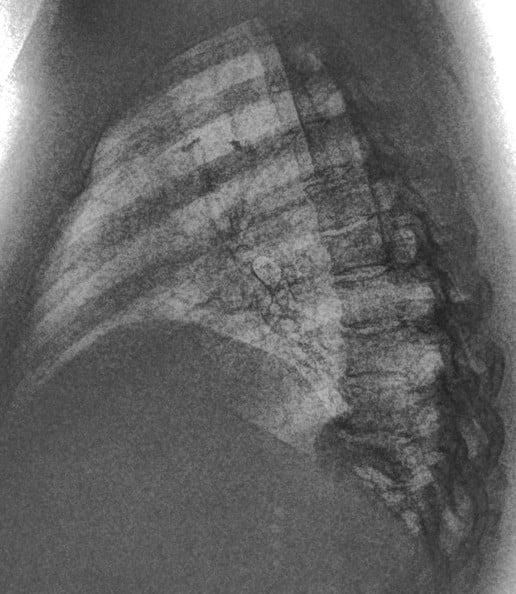

This 67-year old female patient presented to the ER with shortness of breath, in conjunction with chronic pain in her posterior thoracic region upon taking a large breath in. The reading radiologist noticed a suspicious mass-like opacity in the Lateral view. The radiologist stated that, thanks to the DE images, they could they tell the opacity wasn’t a lung mass, but instead far less concerning bony outcroppings from the thoracic vertebrae.